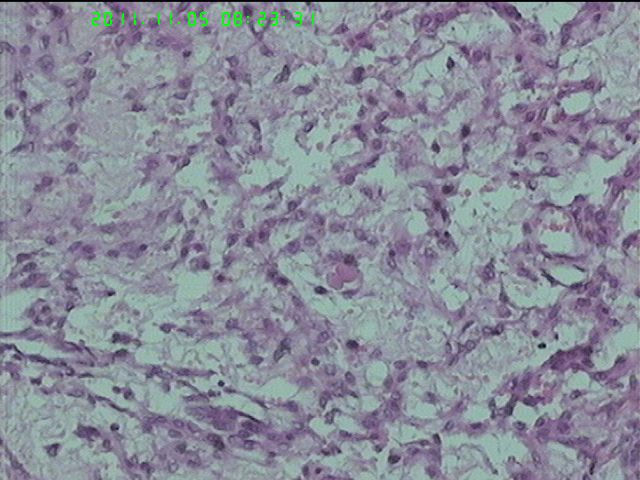

37岁女性患者,左卵巢肿块术中快速:恶性。术后左卵巢囊实性肿块14*9*5CM,灰黄色,部分乳头状,粘液样外观;子宫内膜厚1.5CM;网膜见多个小结节。图1--14左卵巢  15-19网膜  20--23宫腔

在图中有明确浸润吗?好像看不出来,但是网膜显示非侵袭性。宫腔图片没有显示浸润。请多上边缘处图像。

请临床查有无阑尾病变,排除阑尾肿瘤转移后,如果没有明确浸润,倾向粘液性*交界性肿瘤伴腹膜种植,肠型。

总之先排除阑尾来源,再看有无浸润,有浸润才打癌。

图1、4、5、6、11中可见疏松组织,网状结构,并见可疑透明小体,加上患者年纪较年轻,卵黄囊瘤不能除外,粘液腺结构可能是卵黄囊中的内胚层成分。且形态上与网膜结节相似。